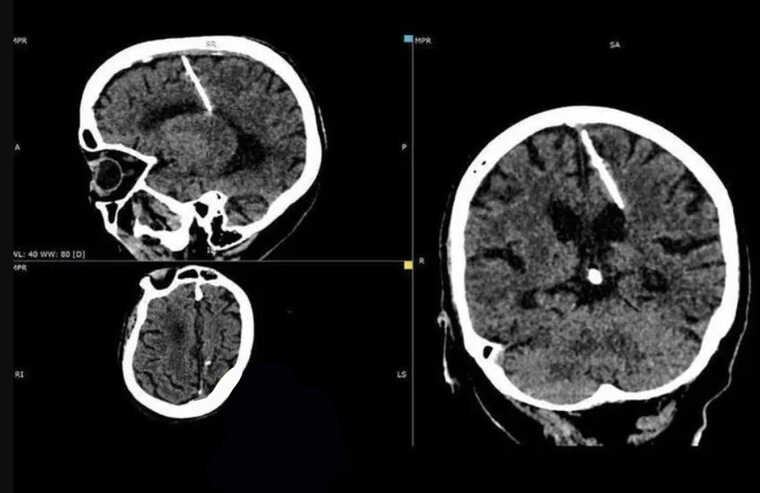

У мозку 80-річної мешканки Сахаліну (РФ) виявили трисантиметрову голку.

Стороннє тіло помітили під час комп’ютерної томографії. На думку лікарів, голку їй у голову встромили батьки після її народження. Таким чином вони хотіли позбутися дитини.

«Такі випадки у голодні роки були не рідкістю: немовляті у тім’ячко вставлялася тонка голка, яка ушкоджувала мозок. Тім’ячко швидко затягувалося, приховуючи сліди злочину, а малюк гинув», — зазначили в обласному МОЗ.

Голка проникла у ліву тім’яну частку. Очікуваних наслідків не сталося – дівчинка вижила. Більше того, згодом її ніколи не мучив головний біль. Стороннє тіло виявили лише цього року.

Оскільки здоров’ю пацієнтки нічого не загрожує, голку вирішили не виймати.